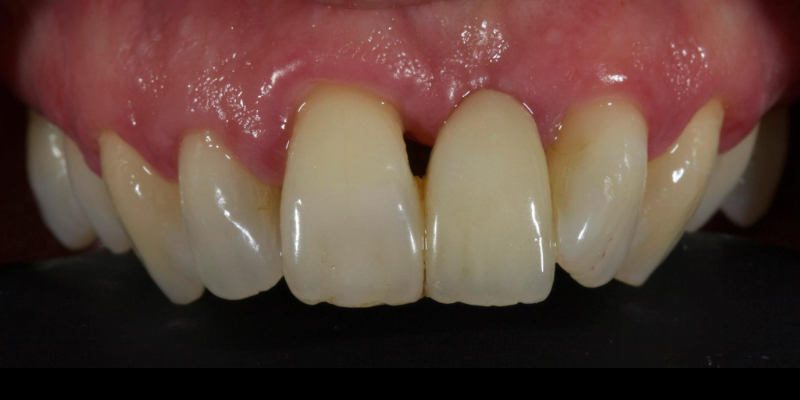

Take Arthur, a 76-year-old man who presented with a vertical root fracture of his upper left central incisor. His medical conditions precluded his request for an implant, so he agreed to the proposal for an adhesive bridge instead.

The tooth was extracted and for four months the pontic site was conditioned with a removable Essix-type of denture (Fig. 1).

An e.max (lithium disilicate), one-wing (adjacent central being the retainer) bridge was placed, which resulted in an acceptable outcome (Figs. 2-4) that was more timely and at a lower financial and biological cost to the patient than the implant Arthur initially thought he wanted.